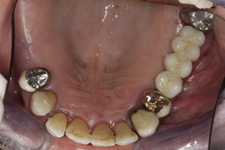

V případě chybění většího počtu zubů v postranních úsecích čelistí je možné ošetření pomocí implantátů, které nahradí ošetření pomocí snímacích náhrad kotvených na zbývajících zubech nebo patře.

Podmínkou je opět dostatečné množství kosti.

Protetické řešení může být pomocí můstku, který je kotvený na implantátech nebo pomocí jednotlivých korunek na implantátech.